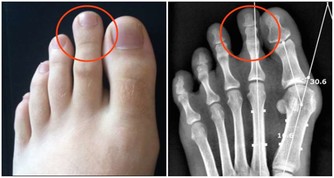

而尿騷味,則通常提示腎有問題了。

另外,一些慢性腎衰病人還有一些特殊的臨床表現,如口腔內有氨的氣味,也就是你說的尿味,尿毒症病人更為明顯。

主要原因是,隨著腎功能的減退,腎臟的溶質清除率下降和某些肽類激素的滅活減少,造成多種毒素在血液和組織中蓄積,最常見的毒素就是尿素等。

在口腔中,因為唾液中的尿素被分解為氨,故病人呼出的氣體有尿味。

這種氣味的濃淡隨病情的進退而變化,在病情好轉時,口中尿味淡些,病情加重時尿味變濃。